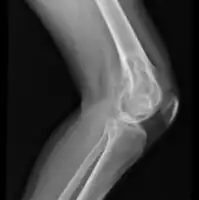

| X-ray knee - chondromyxoid fibroma in long bone of thigh near the knee | |

Chondromyxoid fibroma is a non-cancerous cartilaginous tumor, a type of bone tumor.[2][4] It usually presents with pain and swelling in a long bone of the leg in an adolescent.[1][3]

It is rare, comprises <1 % of all bone tumors that arise from bone itself and <2% of cartilage tumors.[2] Around half occur around the knee and mostly in long bone of lower leg in the teens.[2]